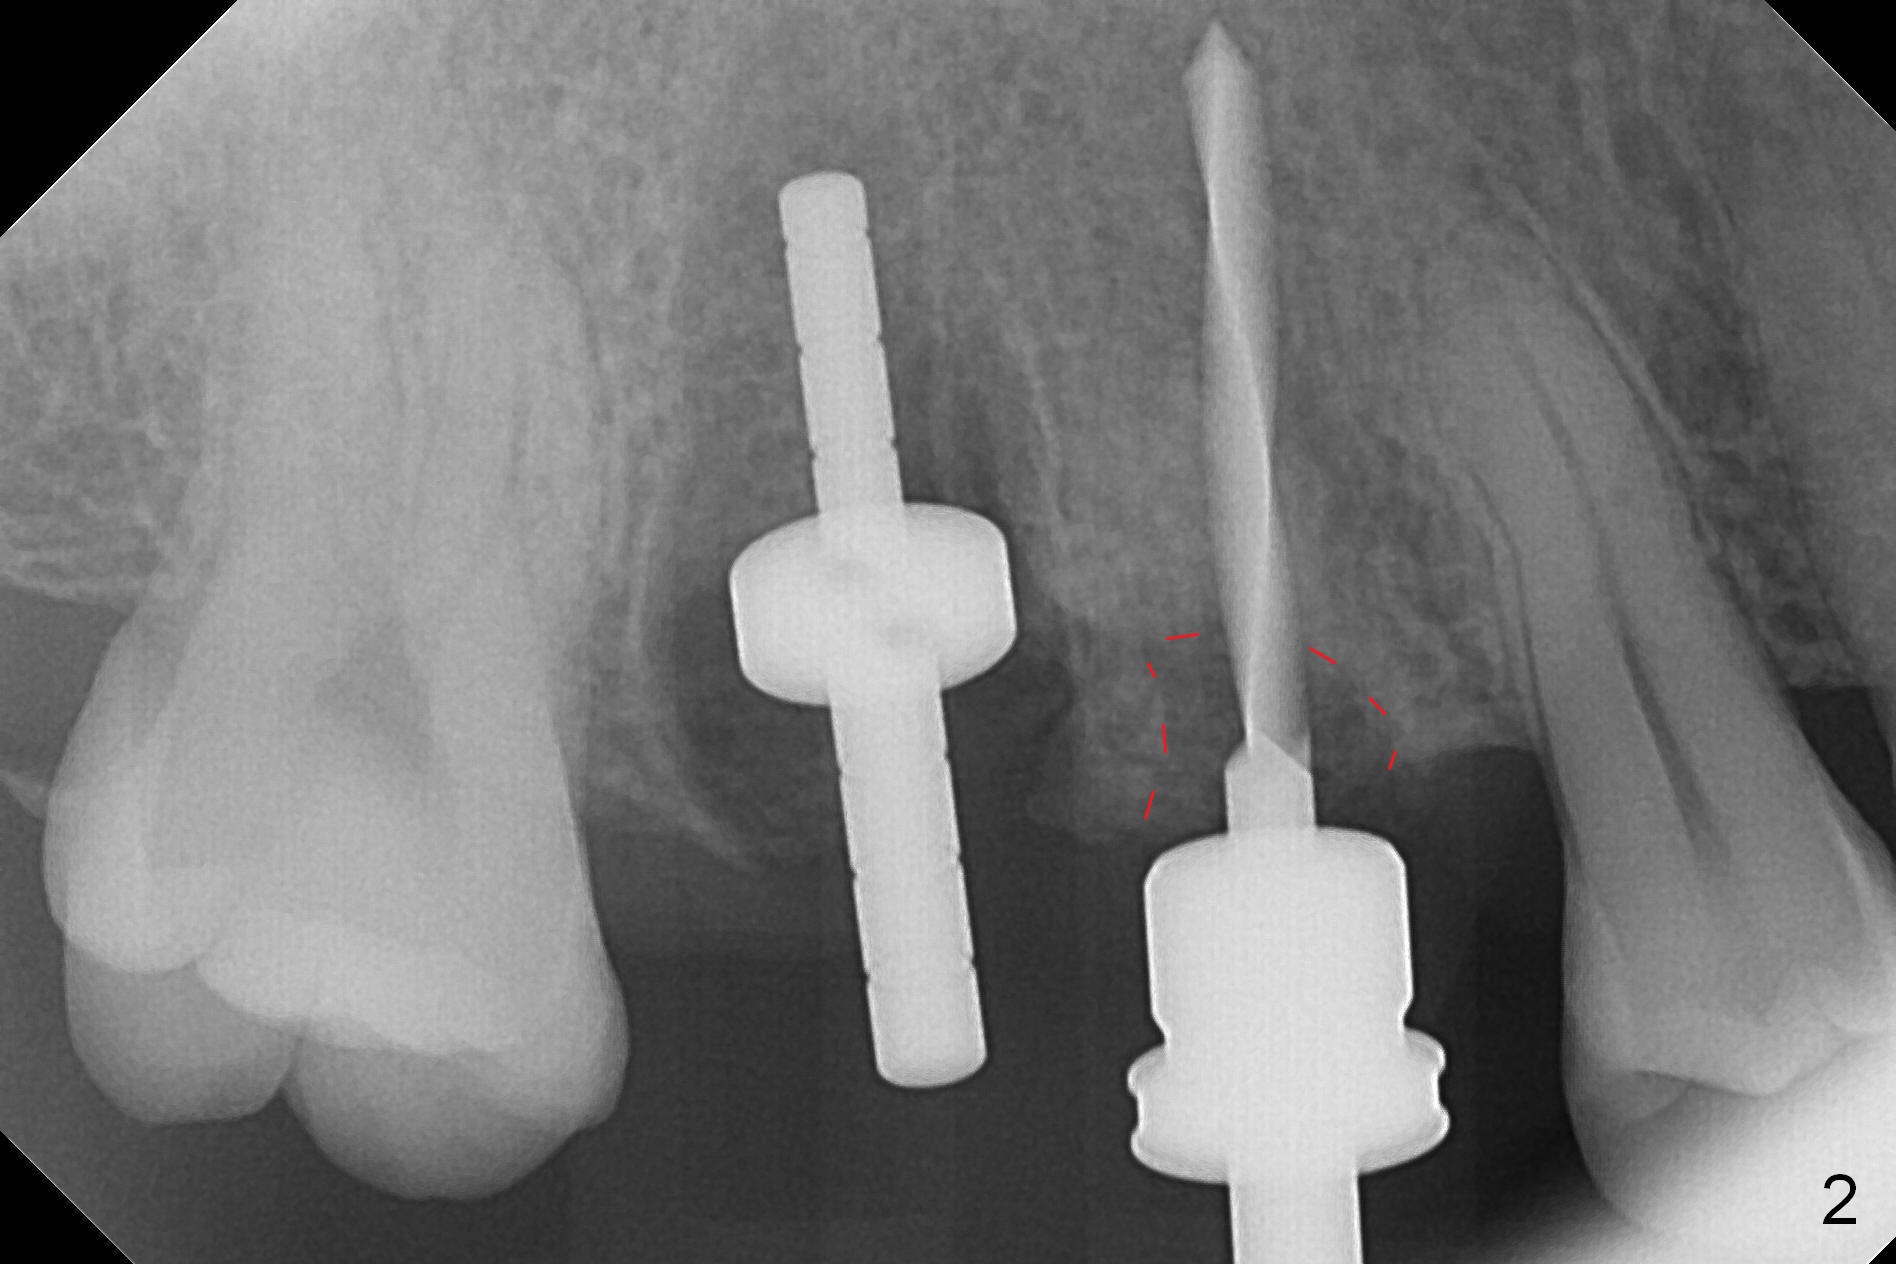

After extraction, osteotomy is established in the septum of #3 and the mesial slope of the shallow socket of #4 (Fig.2 red dashed line) for 11 and 13 mm deep, respectively. Since the septum is sloped palatally, a series of Magic Drills (MD) are used. A single large MD may wobble in the slope. By the time MD 3.8 mm is used, there is perforation palatally. The insertion torque of 4.5x13 mm IBS implant is less than 30 Ncm (Fig.3). In retrospectively, the osteotomy should have been initiated more buccally or deeper, since there is fair amount of clearance from the sinus floor (Fig.5 ^). The implant at #9 is 3.8x16 mm.